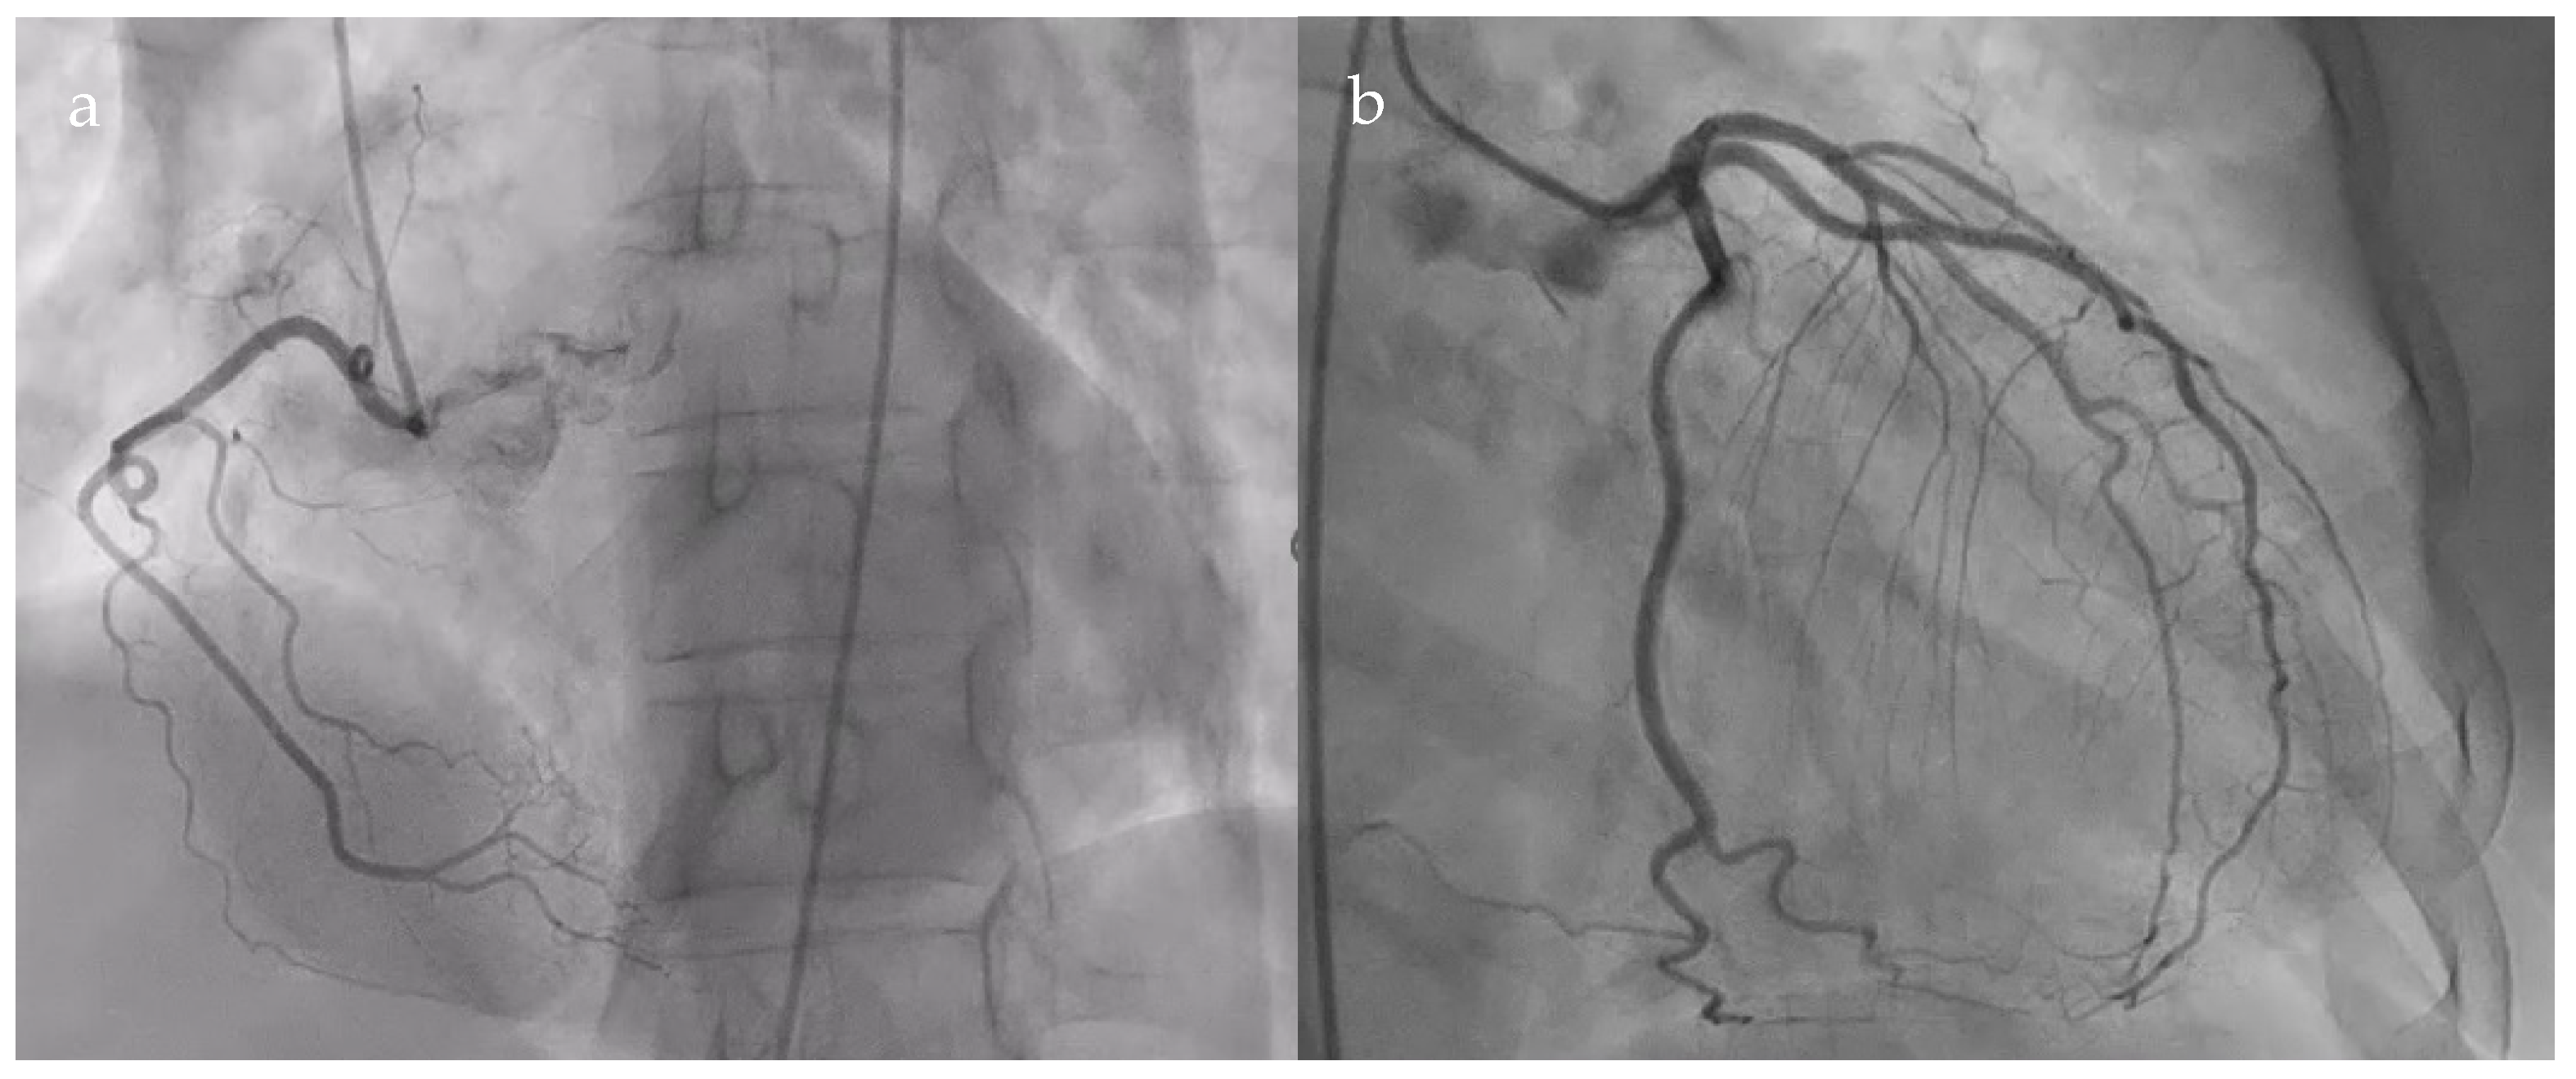

Follow-up transthoracic echocardiography revealed an enlargement of the previously noted structure, now measuring 36 × 49 mm, producing the systolic collapse of the right atrium. A saline contrast study confirmed the communication between the right atrium and the pericardial space (Figure 4).

Figure 4.

Transthoracic echocardiography. (a). Subcostal view: right atrial diverticulum 36 mm × 49 mm; (b). 4-chamber apical section: right atrial diverticulum with systolic collapse of the right atrium (red arrow); (c). Saline contrast test—subcostal section: communication between right atrial diverticulum and right atrium (red arrow) (RA—right atrium; RV—right ventricle).